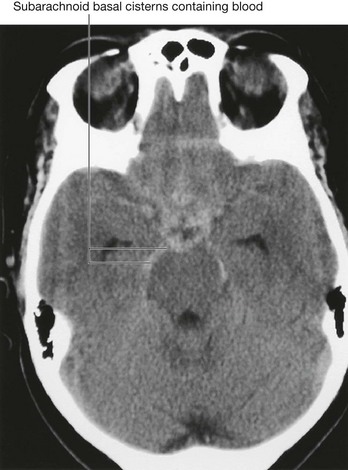

Computed tomography

Since the development of the first computed tomography (CT) scanner, cerebral CT has been the “workhorse” of neuroradiological examination. It is ideally used for head injury because the brain and its coverings can be easily and quickly examined and blood is easily detected. By altering the mathematical algorithm of the data set the bones can also be demonstrated.

With intravenous contrast, CT angiography can be used to demonstrate the position and the size of an intracerebral aneurysm before endovascular treatment.